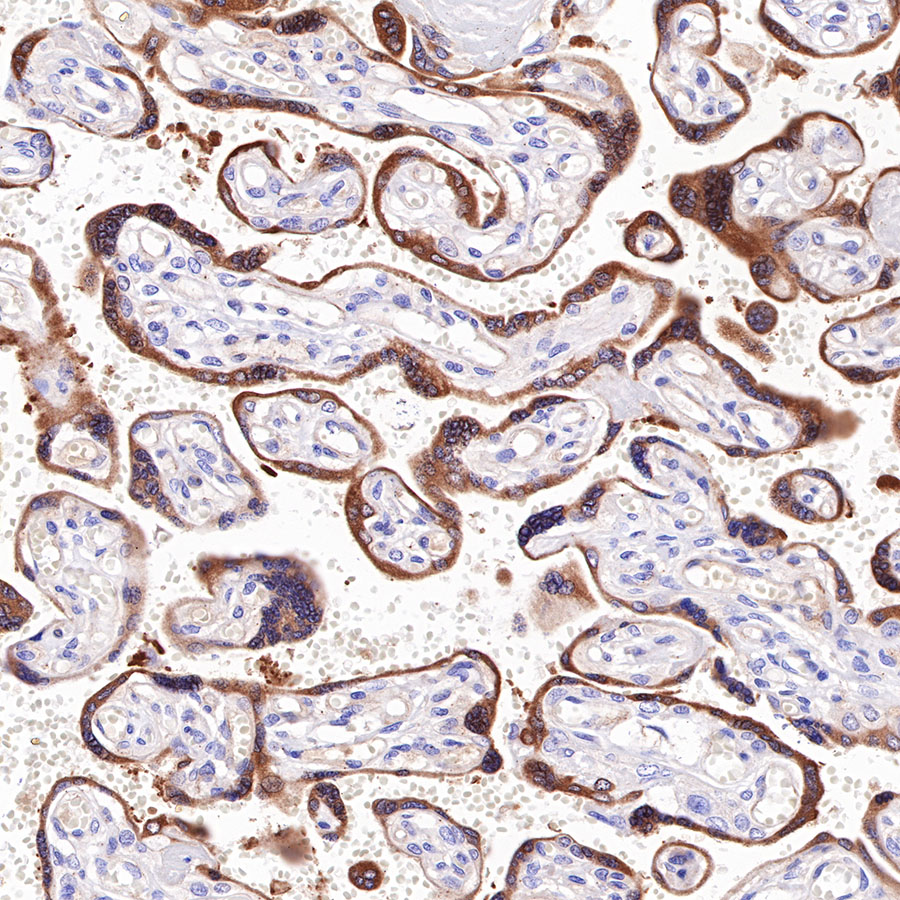

Picture

Immunohistochemistry